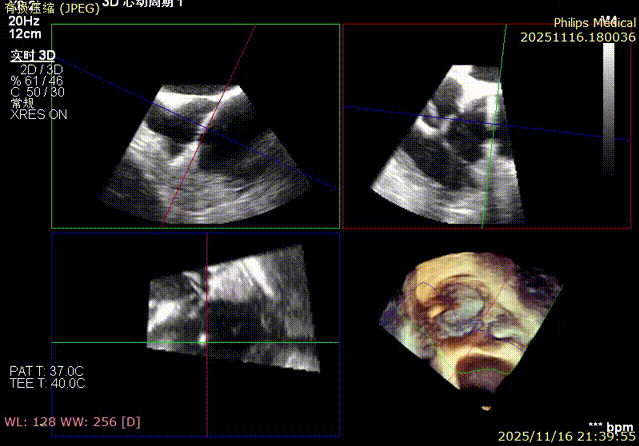

Immediate intraoperative echocardiographic verification showed that the tricuspid regurgitation area was significantly reduced from a preoperative grade of 5+(pre-op) to 2+(post-op), downgrading the severity from extreme to mild-moderate.

Comparison of TR regurgitation severity: reduced from 5+ to 2+

preoperative

postoperative

- TR Severity Comparison: Reduced from 5+ to 2+.

- Annulus Area Reduction: Decreased by 50%.

- Immediate Overall Verification: At the conclusion of the surgery,复查 (re-examination) via TEE confirmed no residual shunt or pericardial effusion around the LAA occluder, and the tricuspid valve repair results were satisfactory. The patient remained hemodynamically stable, marking the complete success of the one-stop procedure.